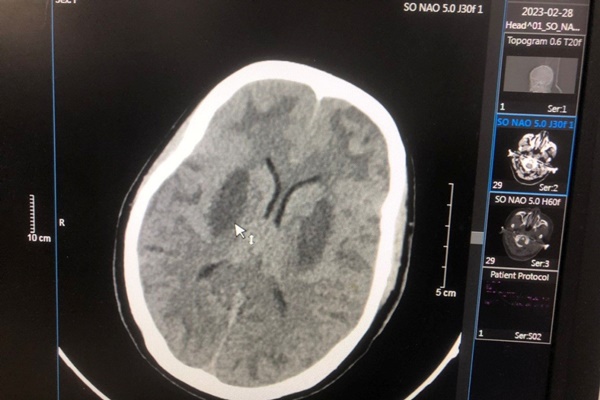

Đến 13 giờ cùng ngày, 4 người gồm bà Nguyễn Thị Thông (40 tuổi), Hồ Văn Tý (28 tuổi), Trương Thị Thương (41 tuổi) và Hồ Thị Điệp (27 tuổi) phải nhập viện cấp cứu trong tình trạng đau đầu, người mệt mỏi, buồn nôn, tê tay chân, khó thở, mắt mờ…

Sau quá trình điều trị tại Trung tâm y tế huyện Phước Sơn, các bệnh nhân này được chuyển đến Bệnh viện Đa khoa Khu vực miền núi phía Bắc Quảng Nam (đóng ở huyện Đại Lộc) để tiếp tục điều trị.

Tuy nhiên, đến ngày 13/3, bà Thông tử vong tại bệnh viện. 3 bệnh nhân còn lại hiện tại sức khỏe đã ổn định, ăn uống được, vẫn đang được điều trị tại bệnh viện.